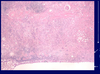

Normal kidney tubules and glomerulus

Interstitial fibrosis; seen in Chronic TID; fibrinous tissue is very pale and separates the renal tubules

Tubular atrophy; tubules shrink in diameter, the epithelium simplifies and the basement membrane thickens; seen in Chronic TID where tubules atrophy in response to slow ischemia

Chronic inflammation; uniform small lymphocytes which are remnants of a previous active inflammation. Seen in Chronic TID.

Chronic TID; fibrosis of interstitium; tubular atrophy

Chronic interstitial nephritis; with fibrosis, atrophy and chronic inflammation